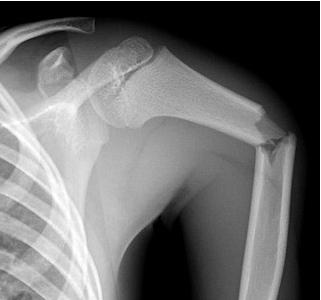

ПІСЛЯ АВТОМОБІЛЬНОЇ АВАРІЇ НА РЕНТГЕНОГРАМІ ВИЯВЛЕНО ПЕРЕЛОМ КІСТКИ В ДІЛЯНЦІ ХІРУРГІЧНОЇ ШИЙКИ. ЯКА КІСТКА МАЄ ТАКУ ШИЙКУ?

варіанти відповідей

Запитання 10